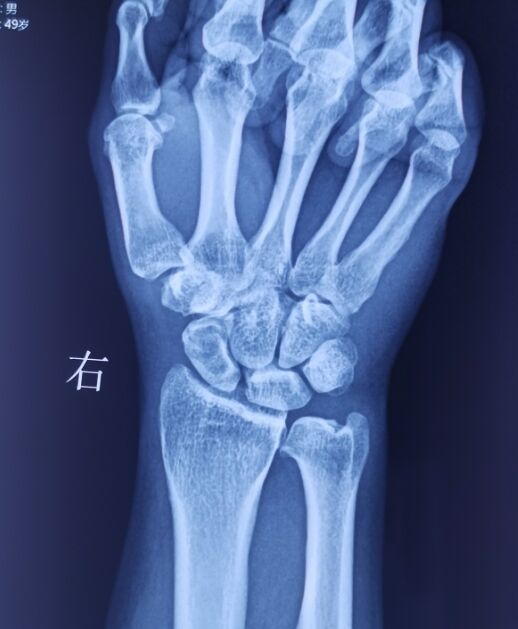

腕关节骨性关节炎

SLAC分期:

I期,舟骨窝局限性关节炎始于桡骨茎突

II期,发展到近端舟骨窝

III期,进而出现头月关节炎

IV期,全腕关节炎

该病例需要做CT重建

判断腕关节骨性关节炎分期

根据分期决定具体术式